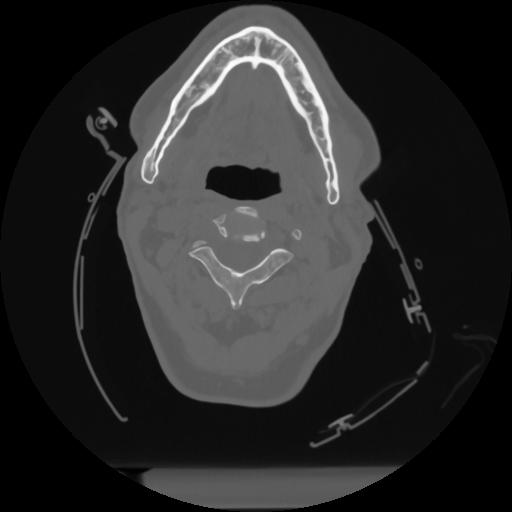

12 P.BLANDAS,,Vol,0.5,P.BLANDAS,,